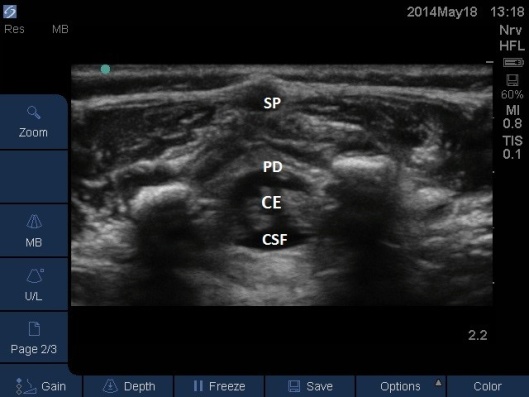

Fig 7. Ultrasound Probe in Midline Transverse position over the sacrum. CE = cauda equina. CSF = ceerbrospinal fluid (anechoic), PD = posterior dura (hyperechoic), SP = spinous process.